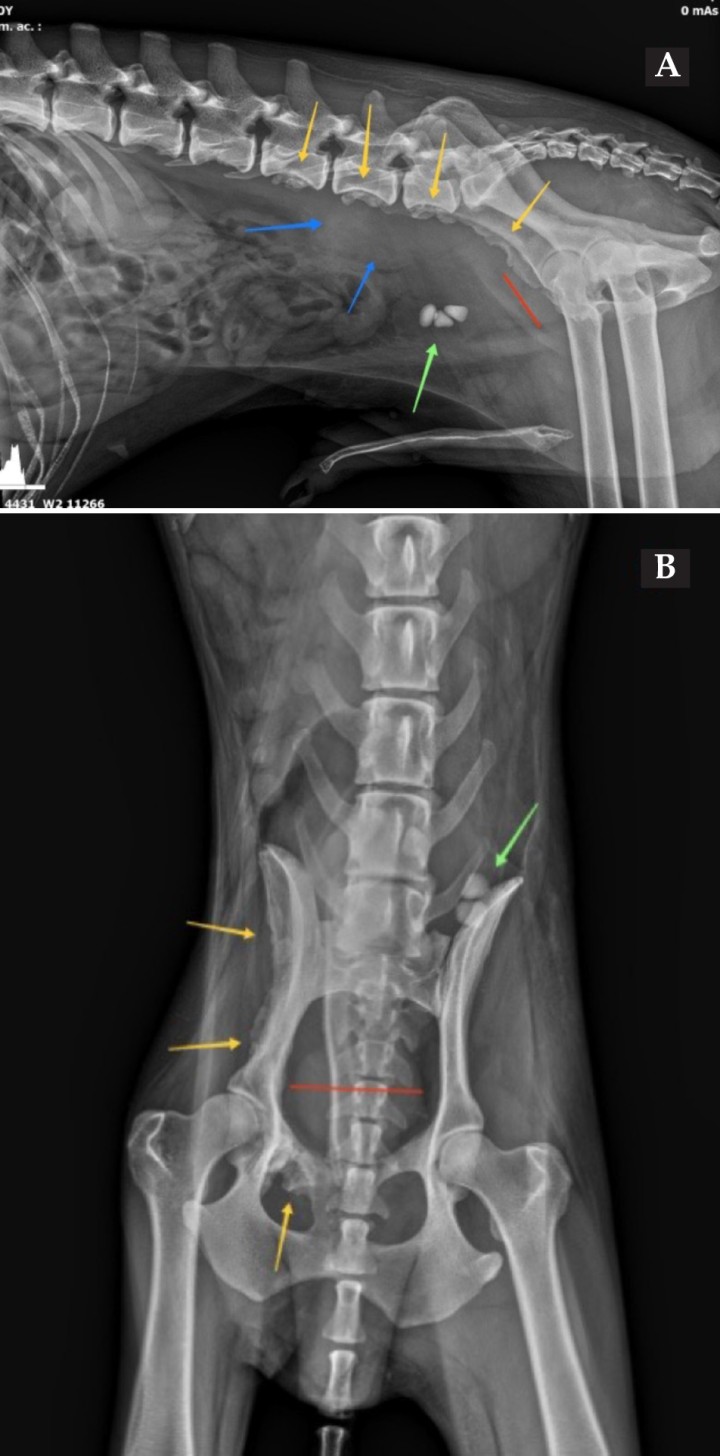

<p>Mismas imágenes que la Figura 1. En ambas proyecciones (<strong>A</strong> y <strong>B</strong>) se observan 3 urolitos en vejiga de la orina (flecha verde), prostatomegalia (línea roja) y lesiones osteoproliferativas en el borde ventral de los cuerpo vertebrales de L5-L6-L7, ilion y pubis (flechas amarillas). En proyección lateral derecha (<strong>A</strong>) se aprecia un aumento focal del tamaño y opacidad del retroperitoneo ventralmente a L6-L7 (flechas azules).</p>

Mismas imágenes que la Figura 1. En ambas proyecciones (A y B) se observan 3 urolitos en vejiga de la orina (flecha verde), prostatomegalia (línea roja) y lesiones osteoproliferativas en el borde ventral de los cuerpo vertebrales de L5-L6-L7, ilion y pubis (flechas amarillas). En proyección lateral derecha (A) se aprecia un aumento focal del tamaño y opacidad del retroperitoneo ventralmente a L6-L7 (flechas azules).

Ventralmente a los cuerpos vertebrales de L6 y L7 se visualiza un aumento focal de tamaño del espacio retroperitoneal con opacidad tejido blando que provoca desplazamiento ventral del colon descendente.

La vejiga de la orina, parcialmente distendida, presenta 3 estructuras redondeadas y de opacidad mineral. Caudalmente a la misma, se visualiza la silueta de la próstata aumentada de tamaño, excediendo el 70 % de la distancia entre el promontorio del sacro y el pubis.

Los signos radiológicos descritos en esta patología y que fueron encontrados en el caso expuesto fueron prostatomegalia,[ Atalan, G., Barr, F. J., & Holt, P. E. (1999). Comparison of ultrasonographic and radiographic measurements of canine prostate dimensions. Veterinary radiology & ultrasound, 40(4), 408-412. [PubMed] ] proliferación ósea, reacción perióstica y aumento de densidad retroperitoneal, con lesión ocupante de espacio. En ocasiones, se pueden visualizar áreas de calcificación en la silueta prostática, hallazgo no encontrado en nuestro paciente.